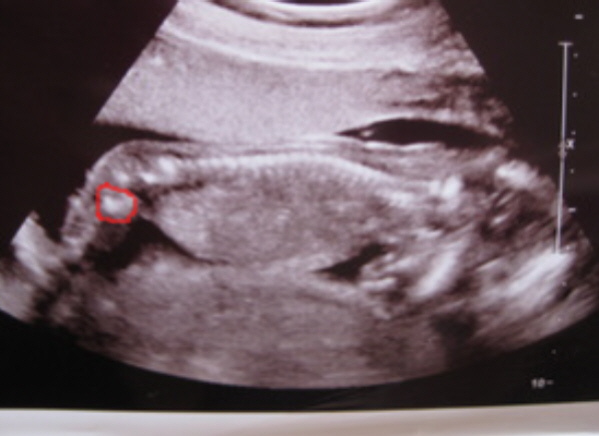

Ahogy ígértem, hoztam a képeket. Igaz Ti idősebbek vagytok a képeken, mert Boti a képeken 14+6 hetes, Ti meg ugye már 17+3 :)

Dodó Pocaklakó Kép

Boti

Kép

Dodó Pocaklakó

Na mazsolázzunk... :D